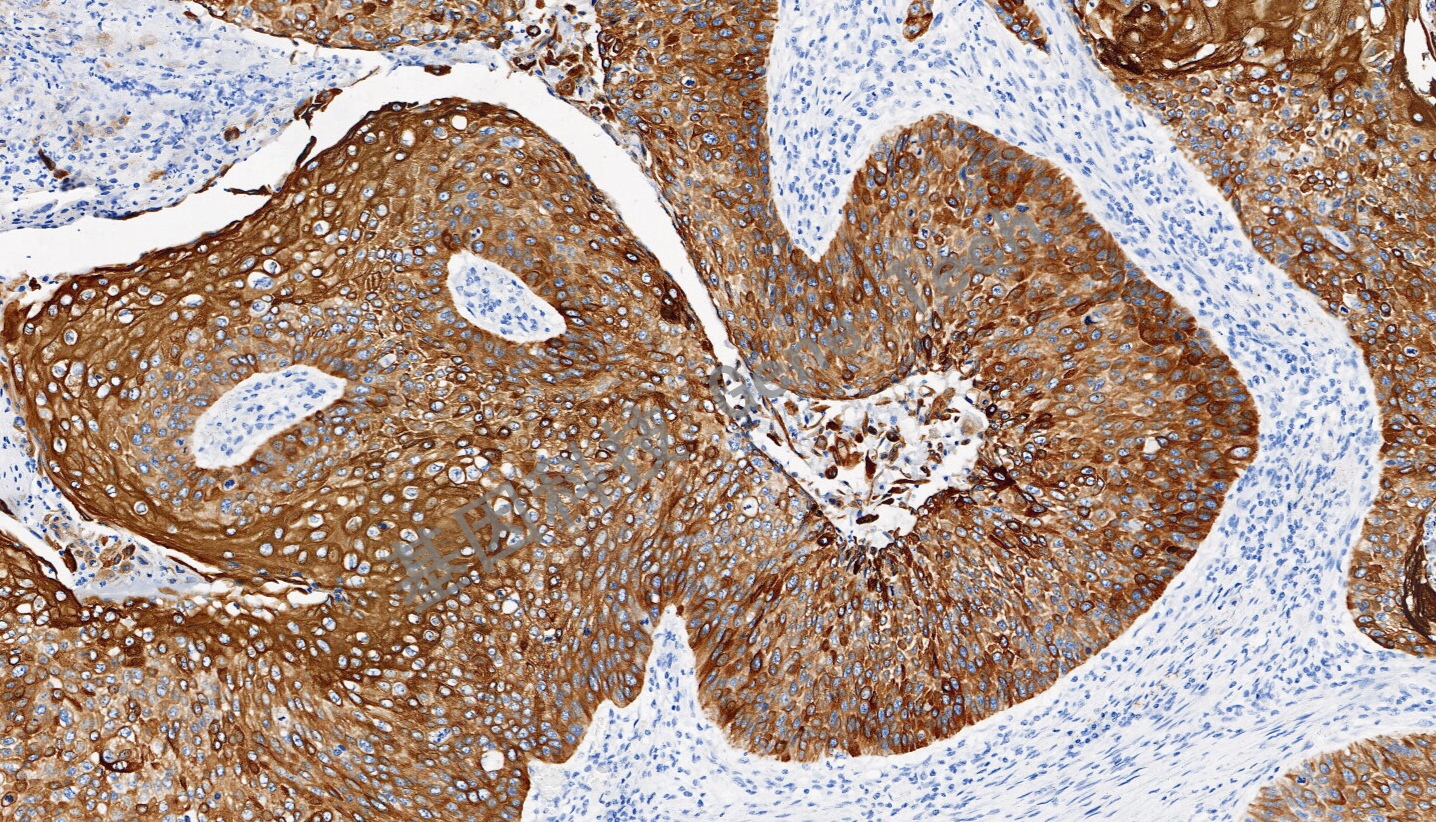

CK6 兔抗人 細胞角蛋白 6(CK6)抗體試劑(免疫組織化學法)

| 簡介:細胞角蛋白6(CK6)是一種上皮特異性的II型角蛋白,通常與創(chuàng)傷后的角質(zhì)細胞活化相關,因此也被認為是一類愈合因子。CK6總是與I型角蛋白CK16和/或CK17成對出現(xiàn),通常在尚未角質(zhì)化的上皮組織的基底層細胞中表達,如口腔粘膜、食道、舌乳頭,在毛囊外根鞘中也有明顯表達。在腫瘤組織中,CK6在多數(shù)的鱗狀上皮癌中表達,特別是在鱗癌癌巢的中間成熟細胞層。CK6通常與CK5一起配套用于鱗癌與腺癌、間皮瘤與腺癌的鑒別診斷,也可用于導管上皮惡性增生的鑒別。 | ||

| 食道癌石蠟切片,用 CK6(GT2490)染色,細胞漿陽性,DAB 顯色。 | ||